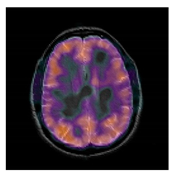

4.1. Criteria and Database

In the experiment, the original color 512 × 512 MRI brain image is from The Whole Brain Atlas [47], which is a publicly available medical images database provided by Harvard Medical School. The other MRI images are from the Internet. In a robust test, the watermark image is a two-value image and the size is 64×64. Here, we select the hospital logo image as the watermark. The original medical host image and the watermark are shown in Figure 4.

Figure 4.

Original medical host image and watermark. (a) Brain, (b) Hands, (c) Spine, (d) Brain, (e) Watermark image.